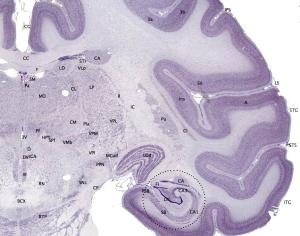

La Struttura è specializzata nella diagnosi e cura delle malattie neurodegenerative come l’Alzheimer, le demenze frontotemporalee vascolare, e delle malattie demielinizzanti come la sclerosi multipla e la neuromielite ottica.

La diagnosi è effettuata utilizzando sia tecniche radiodiagnostiche avanzate, sia l’indagine genetica e biochimica, avvalendosi di un laboratorio di analisi specializzato.